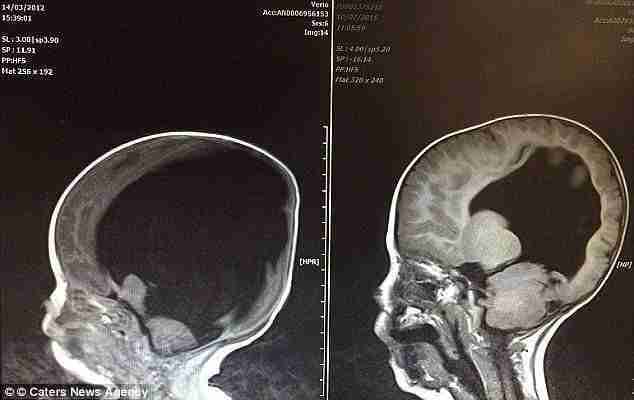

El caso de Noah es sin duda uno de esos milagros que deja a los médicos sin palabras. Antes de nacer, los doctores ya habían advertido a Shelly y a Rob,de 44 años y 50 años de que su hijo nacería con una discapacidad importante. Le aconsejaron a Shelly en cinco ocasiones que abortase, en…